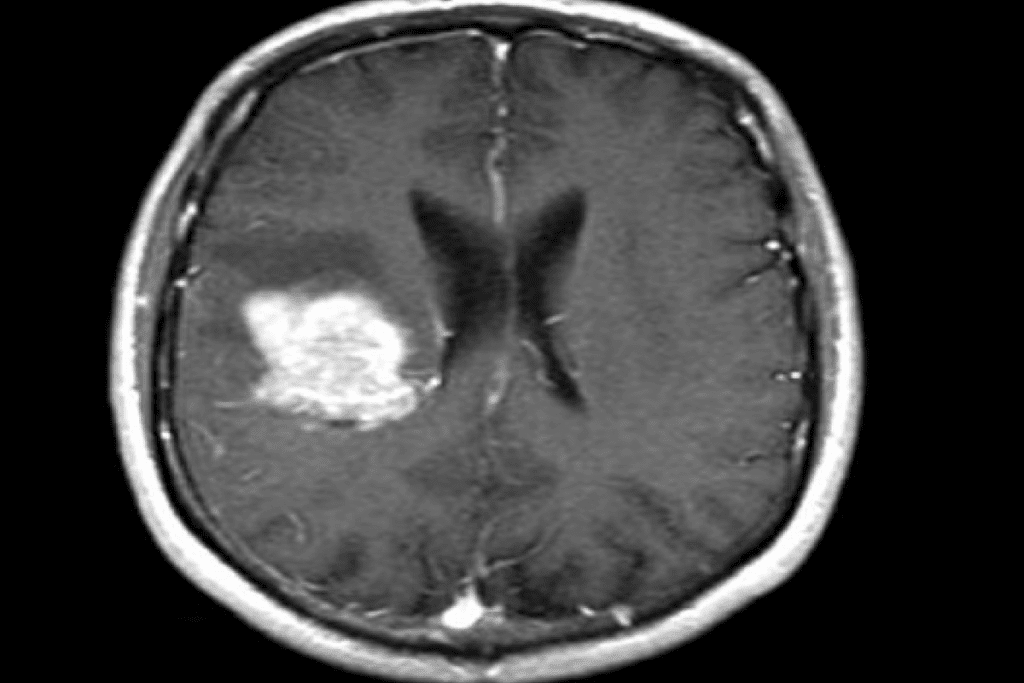

- Magnetic Resonance Imaging (MRI): MRI uses magnetic fields and radio waves to make clear pictures of inside structures. It’s great for soft tissue tumors.

- Positron Emission Tomography (PET) scans: PET scans involve injecting a radioactive tracer. This tracer goes to areas with lots of activity, like tumors, to show where cancer has spread.